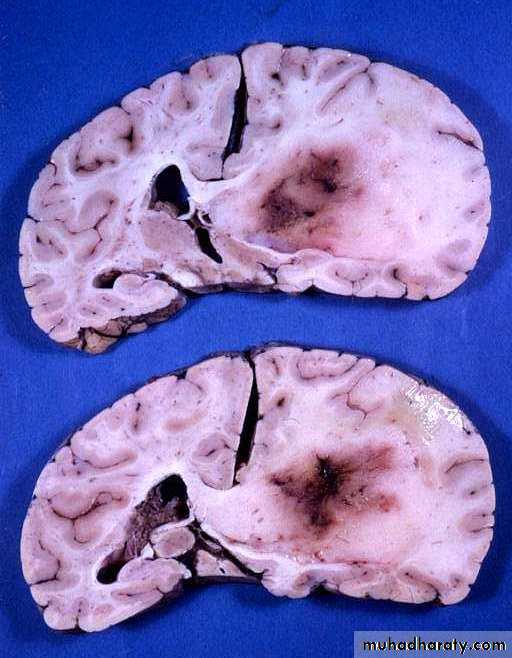

Gliomas

They are derived from cells of glial origin.

• They are the commonest of primary CNS neoplasms.

• They form 50% of adult intracranial tumours.

• They are of four types: astrocytoma, oligodendroglioma, ependymoma and choroid plexus papilloma. The most common of which is astrocytoma.

• Survival is closely associated with grading.

• Treatment involves surgery and radiotherapy and/or chemotherapy.